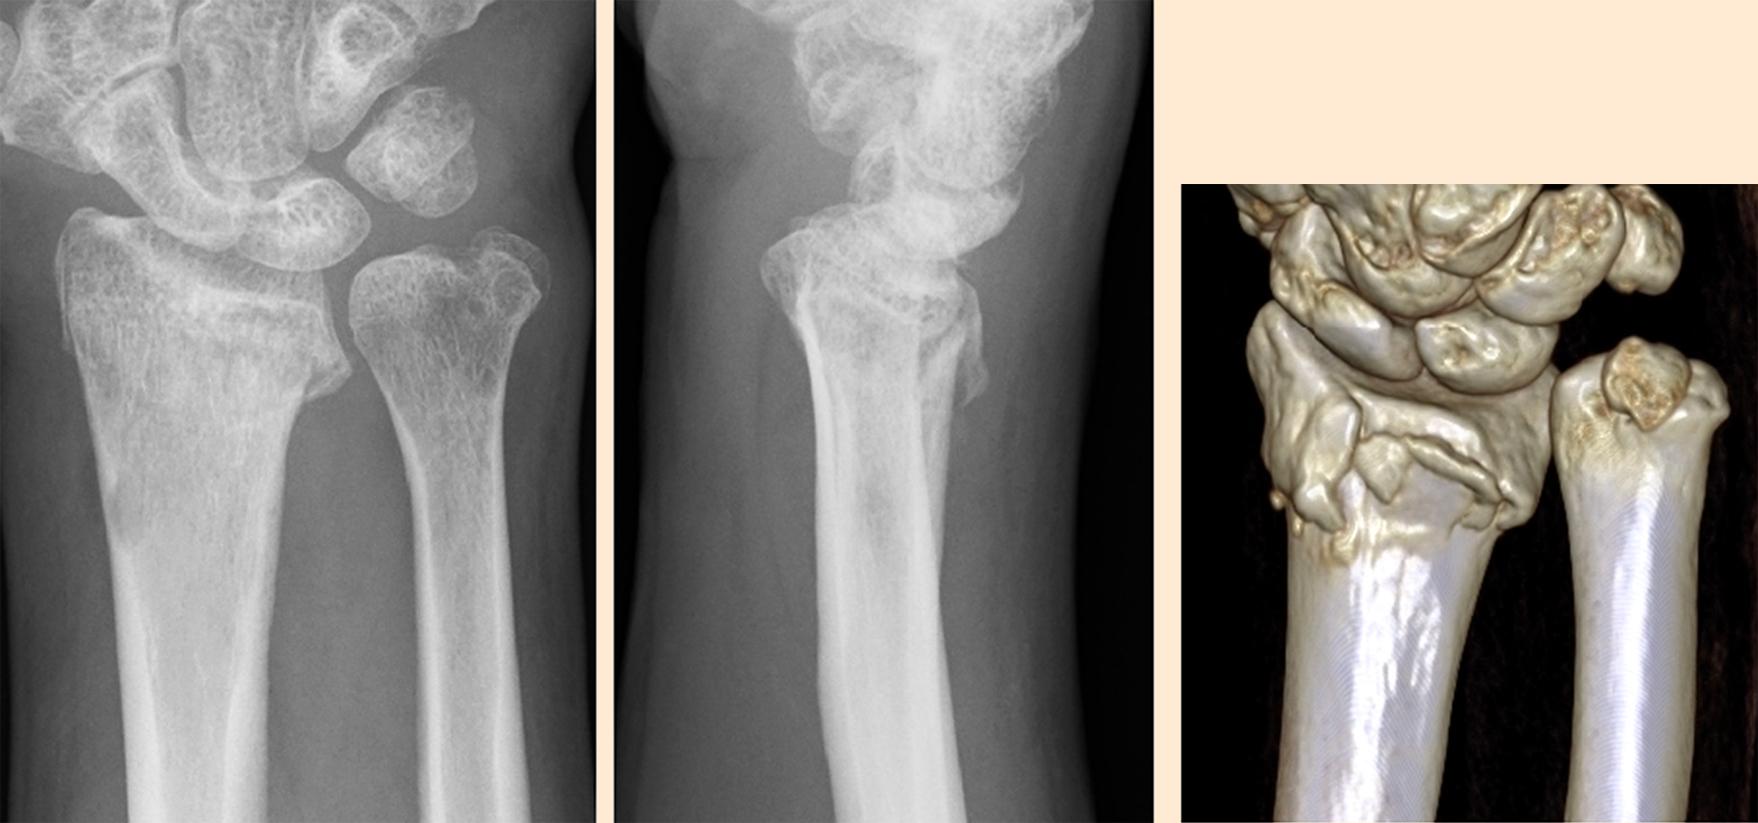

A 56-year-old, right-handed male injured his wrist by falling, was diagnosed with a DRF and treated with cast immobilization. He visited our clinic 3 months after injury with USWP. His radiographs showed a dorsally angulated malunion of the distal radius (RI: 23.5 deg, UV: 5.5 mm, PT: − 27 deg) and an ulnar styloid nonunion ( Fig. 2 ). This nonunion was already diagnosed before the DRF and seemed an old injury. He often felt mild USWP before his DRF. How do you consider the best plan to resolve his USWP?

Fig. 2, Preoperative radiographs and CT showed a shortened and dorsally angulated malunion of the distal radius, and an ulnar styloid nonunion.